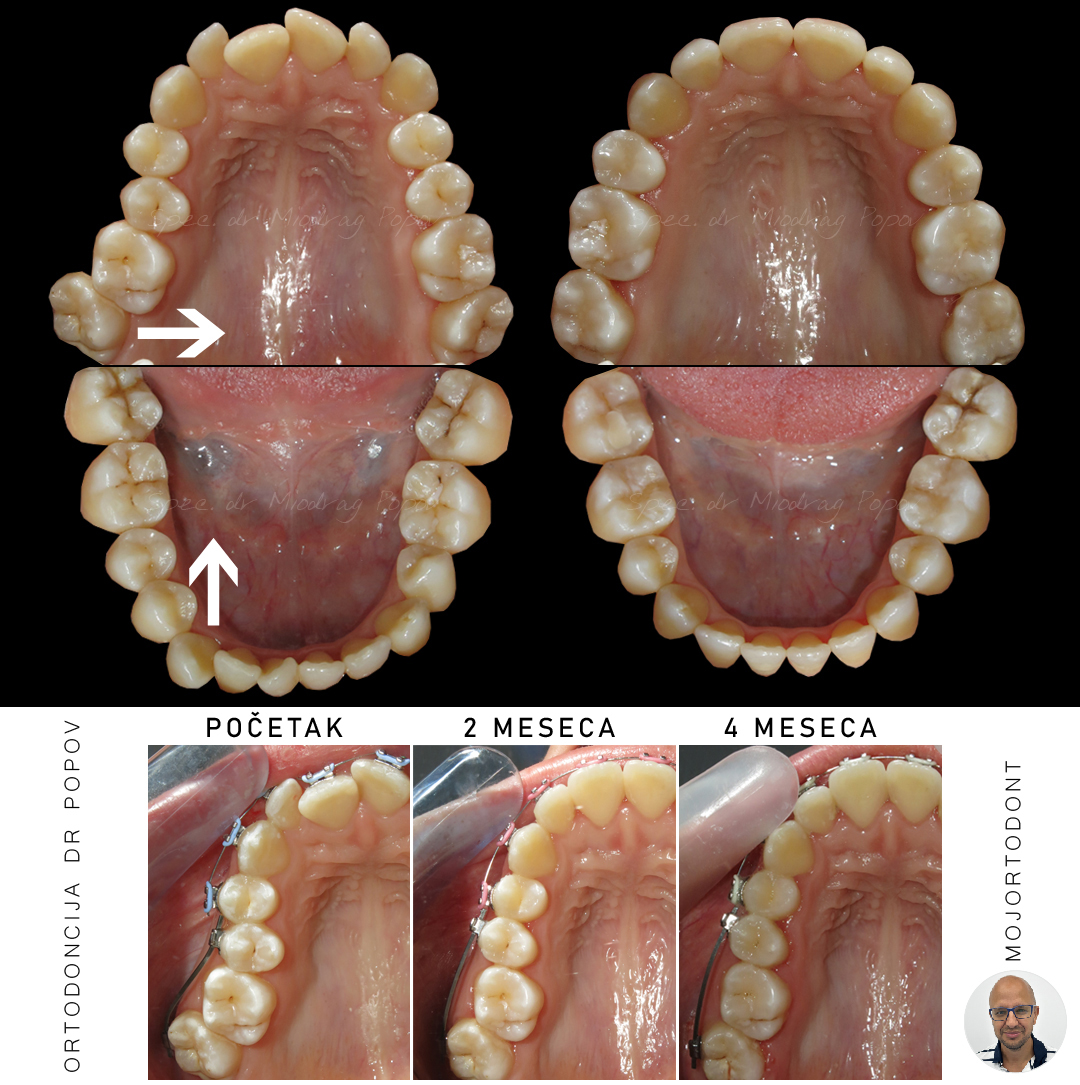

Ova pacijentkinja suočavala se sa ozbiljnim ortodontskim izazovima:

- bukalno promašenim zagrižajem u predelu molara

- teskobom (nedostatkom prostora za smeštaj zuba)

- pomerenim sredinama zubnih nizova

Nakon dve godine posvećene terapije, rezultati su više nego očigledni!

Osmeh je sada harmoničan, zagrižaj je funkcionalan, a svi zubi su na svom mestu.